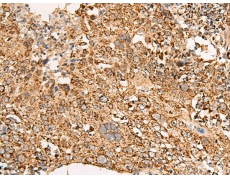

IHC positive control: |

Human cervical cancer and Human colorectal cancer |

IHC Recommend dilution: |

50-300 |